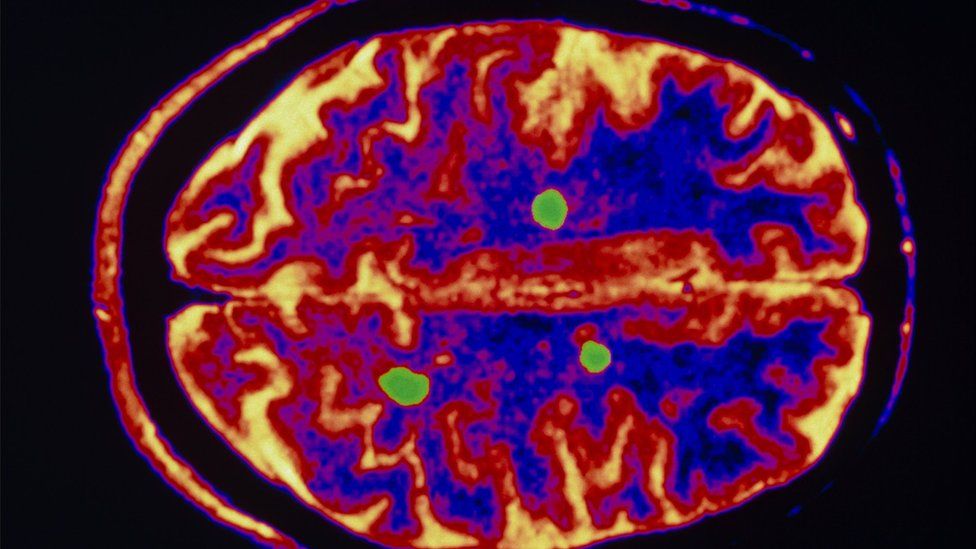

In both forms the immune system attacks the layer of myelin that surround nerves. It acts like the insulation around a cable to allow electrical signals to be passed down the nerve fibre.